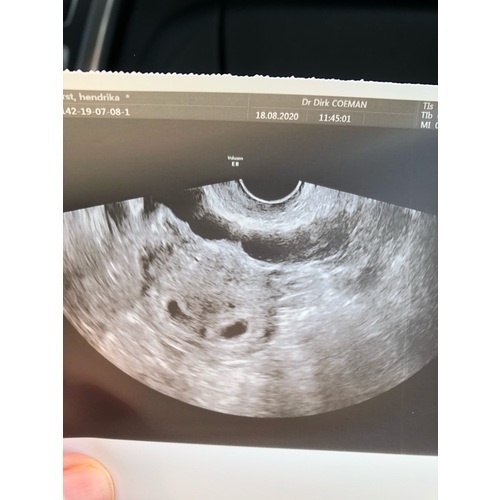

Dit was mijn tweeling echo op 5w5, gaat nog allemaal prima. Morgen 19 weken馃グ

Dit was mijn tweeling echo op 5w5, gaat nog allemaal prima. Morgen 19 weken ...